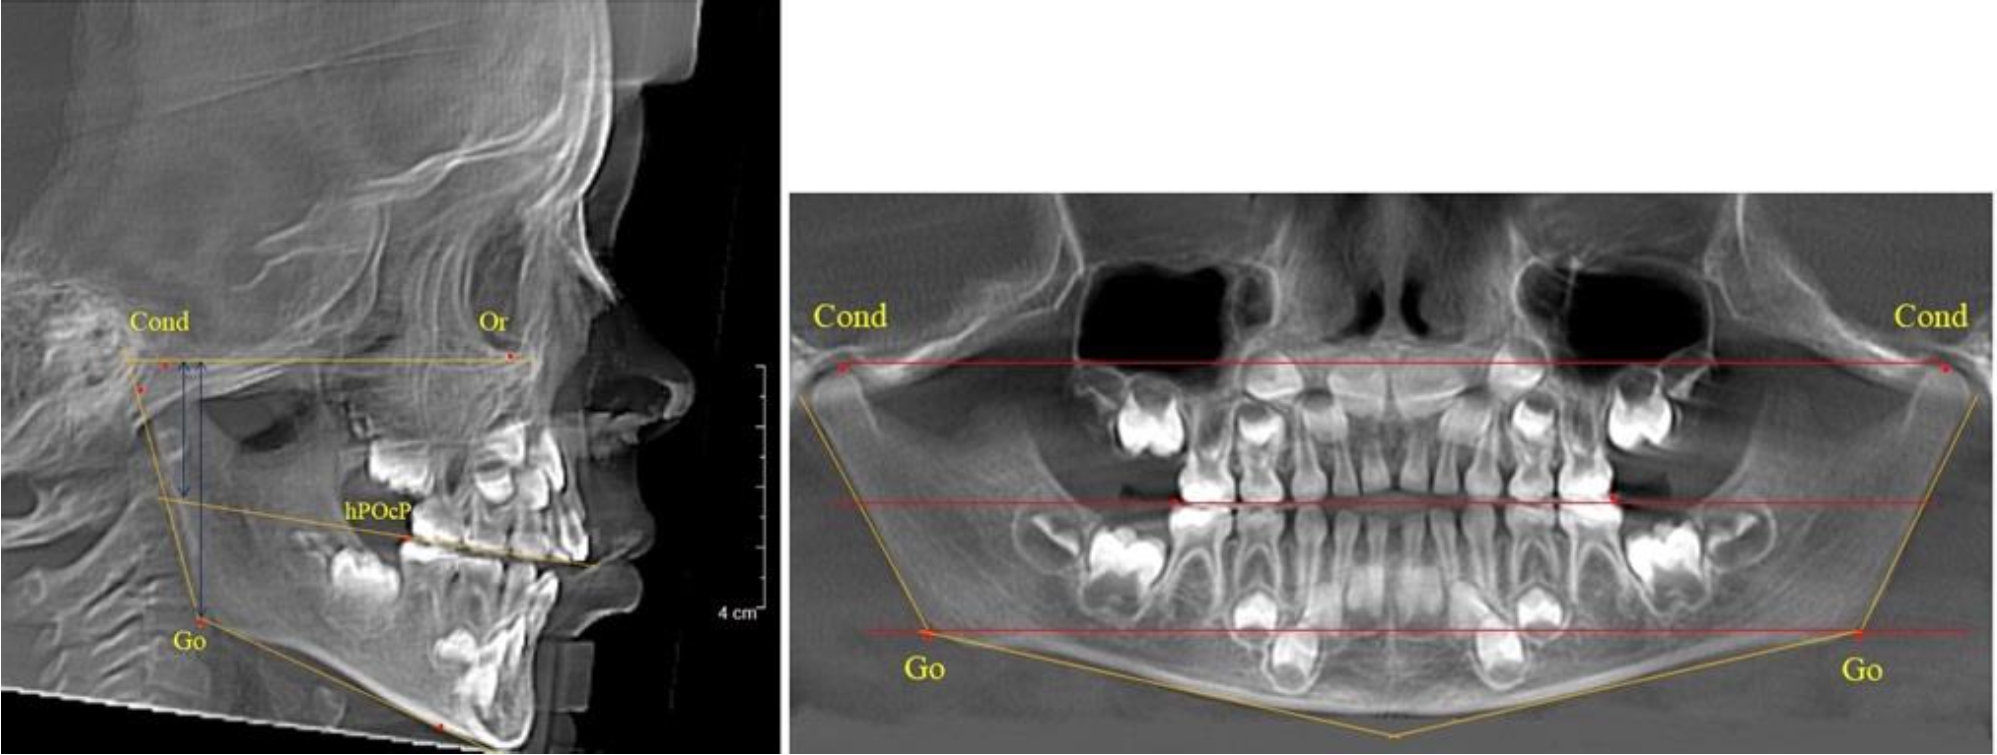

В 1-й группе были проанализированы 7 телерентгенограмм и 7 ортопантомограмм, что составило (6,60 ± 2,41) % от числа изученных рентгенограмм. На всех парах рентгенограмм угол нижней челюсти, измеренный на телерентгенограмме, соответствовал углу, полученному при построении угла на ортопантомограмме. Окклюзионная линия практически однотипно делила ветвь на два отдела (рис. 1).

Как на ортопантомограмме, так и на телерентгенограмме высота ветви у детей в периоде сформированного прикуса молочных зубов составляла (42,21 ± 2,48) мм. При этом высота верхней окклюзионно-суставной части была (22,57 ± 1,46) мм, а нижней – (19,64 ± 1,54) мм.

Учитывая вариабельность абсолютных величин, определи относительные показатели соразмерности частей ветви нижней челюсти. Так, отношение высоты верхней части ветви к нижней в среднем составляло 1,15 ± 0,13. Отношение общей высоты ветви к верхней ее части составляло 1,87 ± 0,14, а отношение общей высоты ветви к нижней ее части было 2,14 ± 0,16 и достоверных различий по относительному показателю отношения всей высоты к верхней и нижней челюсти нами не отмечено (р ˃ 0,05). При этом визуально обе части выглядели примерно равноразмерными.

Рис. 1. ТРГ и ОПТГ пациента 1-й группы

На боковых телерентгенгенограммах вершину суставной головки обозначали точкой кондиион Cond. Касательные линии к ветви и телу нижней челюсти пересекались в точке, которую обозначили Go. Точкой hPOcP обозначали дистальный бугорок нижнего второго моляра вблизи окклюзионного контура коронки. Указанный ориентир соединяли с межрезцовой точкой при построении окклюзионной линии. Высота ветви определялась расстоянием Go-Cond. Окклюзионная линия служила границей между верхней (окклюзионно-суставной) линией и нижней (окклюзионно-альвеолярной) линией.

На ортопантомограмме точки Cond соединяли между собой суставной линией Cond-Cond. Касательная к ветви нижней челюсти соединяла выступающие точки, которые соединялись в области угла и определяли положение точки гонион Go с обеих сторон, которые соединяли гониональной линией Go-Go.

Горизонтальная линя, соединяющая окклюзионные точки hPOcP, определялась как окклюзионная горизонталь.

Расстояние между горизонталями в области ветвей челюсти измеряли электронным штангенциркулем с точностью до сотых долей миллиметра.